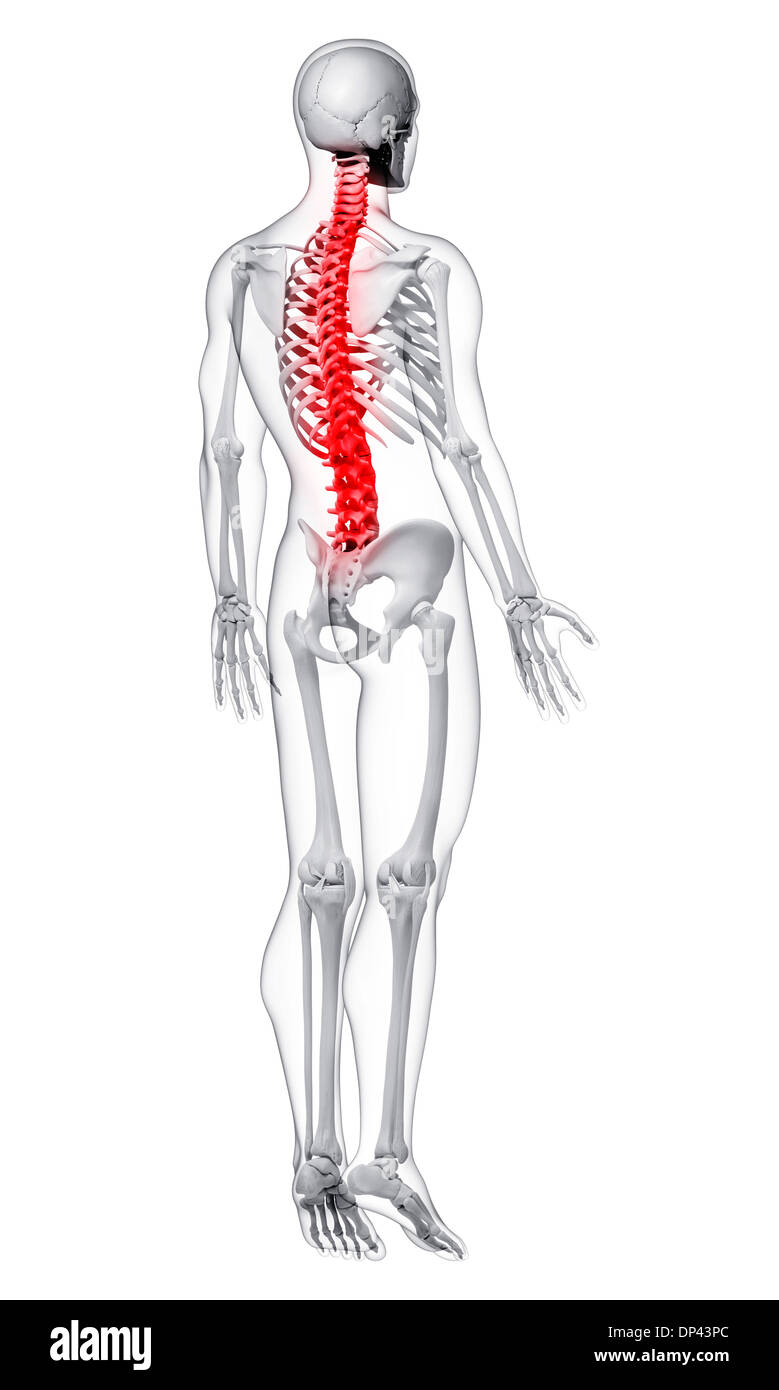

La douleur de la colonne vertébrale, artwork Banque D'Imageshttps://www.alamyimages.fr/image-license-details/?v=1https://www.alamyimages.fr/la-douleur-de-la-colonne-vertebrale-artwork-image65244324.html

La douleur de la colonne vertébrale, artwork Banque D'Imageshttps://www.alamyimages.fr/image-license-details/?v=1https://www.alamyimages.fr/la-douleur-de-la-colonne-vertebrale-artwork-image65244324.htmlRFDP43PC–La douleur de la colonne vertébrale, artwork